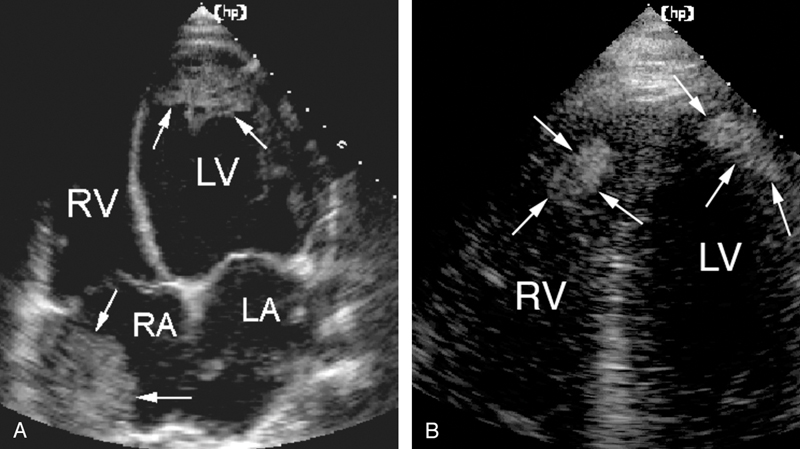

فحوصات تشخيصية لبعض امراض القلب والشرايين التاجية